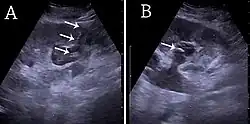

- ^ Content initially copied from: Hansen KL, Nielsen MB, Ewertsen C (December 2015). "Ultrasonography of the Kidney: A Pictorial Review". Diagnostics. 6 (1): 2. doi:10.3390/diagnostics6010002. PMC 4808817. PMID 26838799. (CC-BY 4.0)